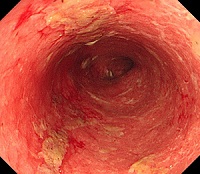

궤양성 대장염 이미지

[궤양성 대장염]